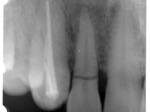

片側2歯欠損 主訴-入れ歯を使ってみたが違和感強くてダメ。固定のものにしたい。術前下顎口腔内(鏡像)